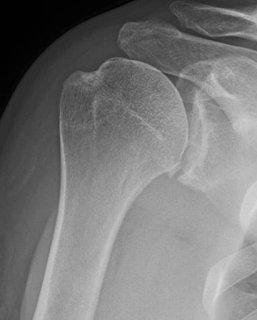

His x-ray on presentation showed only minimal osteophyte formation and no joint space narrowing.

An MRI suggested patchy loss of humeral articular cartilage.